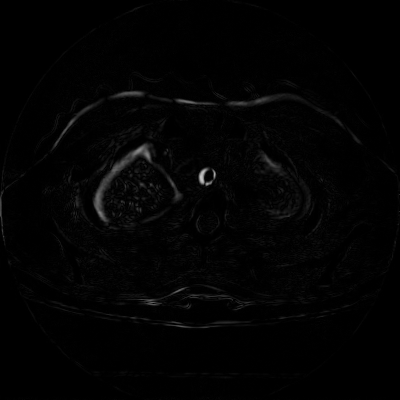

7.3. Real CT images

We then test our method on slices of chest CT images obtained from the Open Access Biomedical Image Search Engine [2]. Fig. 10(a) and 10(b) show the source image and target image respectively, and the intensity difference is shown in Fig. 10(c). The registration result obtained by our proposed method is shown in Fig. 10(d) (see also the result with the deformed underlying grid in Fig. 10(e)). From the final intensity difference plot in Fig. 10(f), it is easily to see that our method matches not only the two large components but also the small dot at the center very well. On the contrary, DDemons [47] produces a suboptimal registration result with a significantly larger mismatch of the small component at the center (see Fig. 10(g) and Fig. 10(h)).